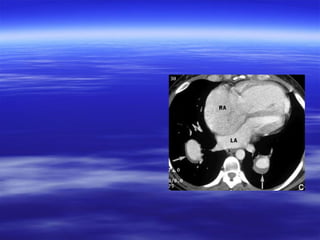

CT findings ooff aaccuuttee ppuullmmoonnaarryy

eemmbboolliissmm

VVaassccuullaarr aabbnnoorrmmaalliittiieess::

 IInnttrraalluummiinnaall ffiilllliinngg ddeeffeeccttss tthhaatt ffoorrmmss aann aaccuuttee

aannggllee wwiitthh tthhee vveesssseell wwaallll && mmaayy bbee ssuurrrroouunnddeedd

bbyy ccoonnttrraasstt mmaatteerriiaall ((ppoolloo mmiinntt ssiiggnn oorr rraaiillwwaayy

ssiiggnn((..

 TToottaall ccuuttooffff ooff vvaassccuullaarr eennhhaanncceemmeenntt..

 EEnnllaarrggeemmeenntt ooff tthhee oocccclluuddeedd vveesssseell..

AAnncciillllaarryy ffiinnddiinnggss::

 PPlleeuurraall bbaasseedd wweeddggee sshhaappeedd aarreeaass ooff iinnccrreeaasseedd

aatttteennuuaattiioonn wwiitthh nnoo ccoonnttrraasstt eennhhaanncceemmeenntt..

CT findings ooffaaccuuttee ppuullmmoonnaarryy eemmbboolliissmm VVaassccuullaarr aabbnnoorrmmaalliittiieess::  IInnttrraalluummiinnaall ffiilllliinngg ddeeffeeccttss tthhaatt ffoorrmmss aann aaccuuttee aannggllee wwiitthh tthhee vveesssseell wwaallll && mmaayy bbee ssuurrrroouunnddeedd bbyy ccoonnttrraasstt mmaatteerriiaall ((ppoolloo mmiinntt ssiiggnn oorr rraaiillwwaayy ssiiggnn((..  TToottaall ccuuttooffff ooff vvaassccuullaarr eennhhaanncceemmeenntt..  EEnnllaarrggeemmeenntt ooff tthhee oocccclluuddeedd vveesssseell.. AAnncciillllaarryy ffiinnddiinnggss::  PPlleeuurraall bbaasseedd wweeddggee sshhaappeedd aarreeaass ooff iinnccrreeaasseedd aatttteennuuaattiioonn wwiitthh nnoo ccoonnttrraasstt eennhhaanncceemmeenntt..  LLiinneeaarr aatteelleeccttaassiiss..